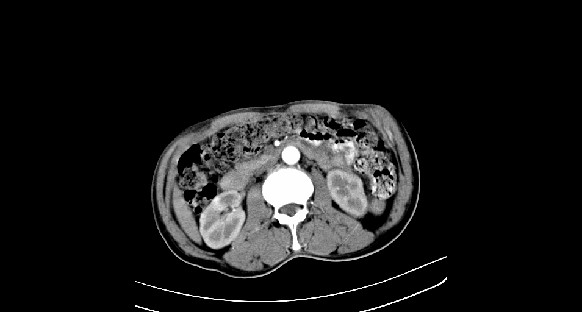

男性,70岁,体检b超发现左肾占位,请各位战友发表一下观点

左肾有两个病灶,且较大的病灶内可见点状钙化灶,增强扫描边缘也是呈渐进性强化,中央部分未见明显强化